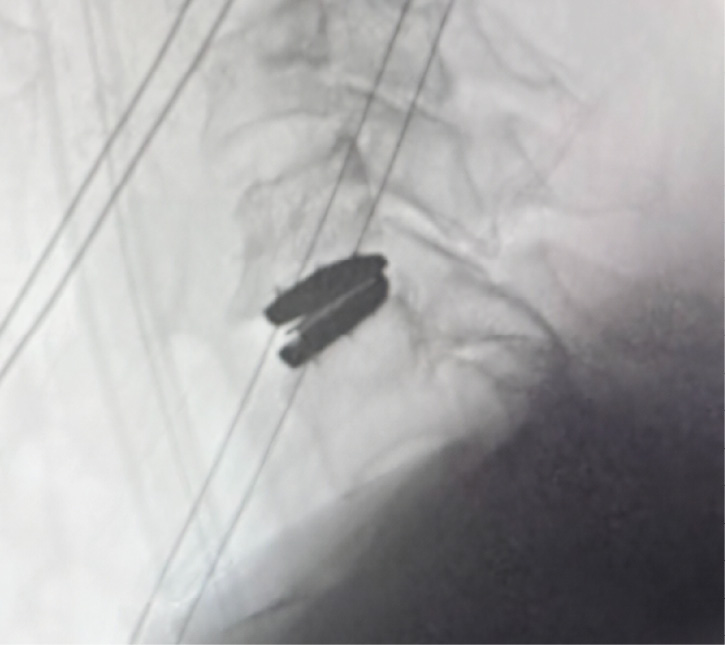

Patient is a healthy, active 58 year-old female, though with advanced degenerative spondylosis at a low cervical level. The patient had favorable anatomy with a long neck and low shoulders to facilitate intraoperative visualization. Fusion was appropriate in this case, but intraoperatively, though we were prepared for this possiblity, the disk space was well-preserved and mobilized without major modification of the endplates. The postoperative flexion and extension radiographs showed movement at the spinous processes of C6/7 and good function of the prodisc C Vivo prosthesis. The adjacent C5/6 level also shows degenerative spondylosis. By optimizing the mobility of the C6/7 level I anticipate the patient will have an improved trajectory for her cervical spine function throughout her life.